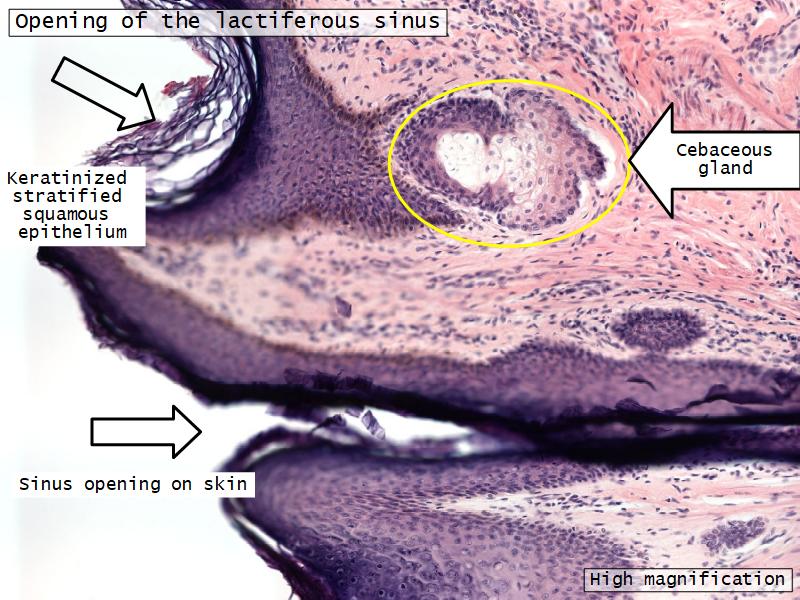

What are the main morphological features of the nipple?

(4)

Morphology

- Covered with skin

- Consists of dense collagenous connective tissue

- Interlaced with smooth muscle fibres

- Contains openings of lactiferous ducts

Skin

- Keratinized stratified squamous epithelium

- Sebaceous glands

Stroma

- Collagenous connective tissue

- Irregular dense connective tissue

- Smooth muscle

- Fibres and bundles

- Lactiferous sinusses

- Stratified cuboidal epithelium